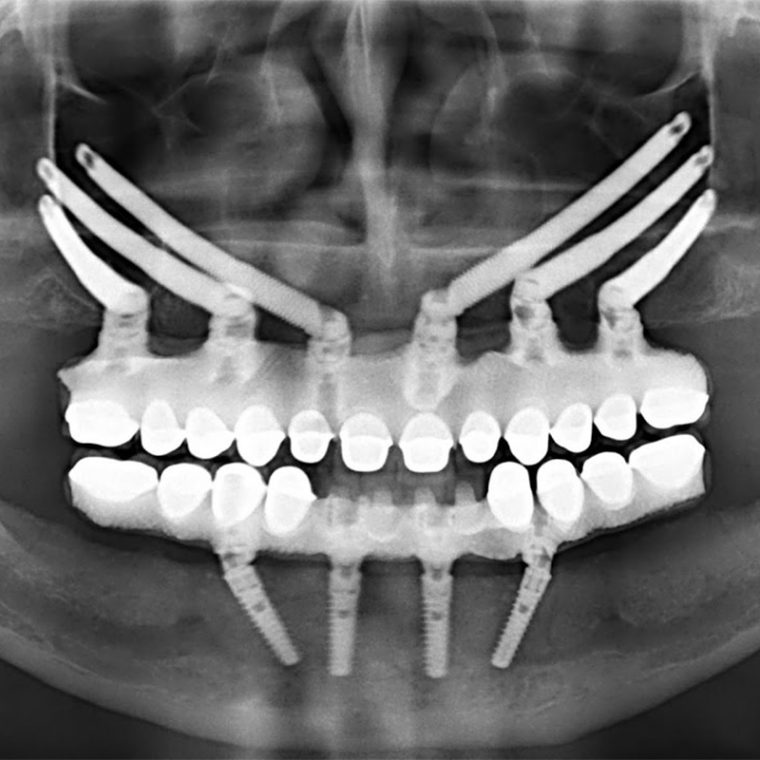

ایمپلنتهای زیگوماتیک نوعی از ایمپلنت دندانی هستند که برای بیمارانی با از دست دادن شدید استخوان در فک بالا استفاده میشوند. برخلاف ایمپلنتهای سنتی که برای تثبیت به استخوان فک نیاز دارند، ایمپلنتهای زیگوماتیک در استخوان زیگوماتیک (استخوان گونه) قرار میگیرند که استخوانی بسیار متراکمتر و قویتر از استخوان فک است. این ویژگی به دندانپزشکان این امکان را میدهد که از نیاز به پیوند استخوانی جلوگیری کرده و راهحل پایدارتر و فوریتری ارائه دهند.

با این حال، ایمپلنتهای زیگوماتیک راهحلی کارآمدتر و مؤثرتر برای این مشکلات ارائه میدهند. استخوان زیگوماتیک در جای بالاتری قرار دارد و تأثیرات فرآیند از دست دادن طبیعی استخوان که فک بالا را تحت تأثیر قرار میدهد، کمتر است. با قرار دادن ایمپلنتها در استخوان زیگوماتیک، دندانپزشکان میتوانند عملکرد و زیبایی را بدون نیاز به جراحیهای پیچیده پیوند استخوانی بازسازی کنند.

فرایند دریافت ایمپلنتهای زیگوماتیک با ارزیابی کامل توسط یک جراح دندان آغاز میشود. با استفاده از فناوری تصویربرداری پیشرفته، مانند سیتی اسکن، جراح ساختار استخوان موجود را ارزیابی کرده و محل قرارگیری ایمپلنتها را برنامهریزی میکند.

روند جراحی معمولاً تحت بیهوشی عمومی انجام میشود، جایی که جراح ایمپلنتها را در استخوان زیگوماتیک قرار میدهد. زمان بهبودی معمولاً از جراحیهای سنتی ایمپلنت کوتاهتر است و بسیاری از بیماران پس از چند روز به فعالیتهای روزمره خود باز میگردند.